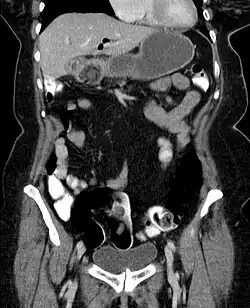

Hinweise auf die Ursache der Beschwerden geben verschiedene bildgebenden Verfahren. Oft gelangt mit Bildung der Fistel Luft in die Gallenwege, was in der Sonographie wie in der Computertomographie und gelegentlich auch schon in der Röntgenübersichtsaufnahme erkennbar ist. Bei einer solchen Aerobilie zusammen mit den Zeichen eines Dünndarmileus und dem Nachweis eines Gallensteins außerhalb der Gallenblase spricht man von der für einen Gallensteinileus typischen Rigler-Trias. Allerdings liegt beim Bouveret-Syndrom der Verschluss unmittelbar am Magenausgang so hoch, dass Zeichen des Dünndarmileus fehlen können. Die Laborwerte sprechen für eine Entzündung und eventuell Elektrolytstörungen.